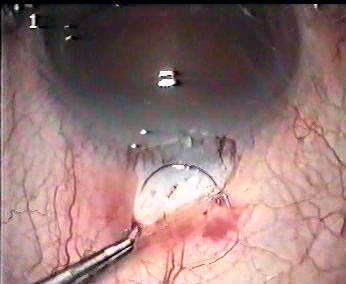

南京鼓楼医院李教授改进的小切口白内障手术录像。通过特殊设计的劈核刀将核分为3块,逐一取出并植入折叠人工晶体。 下载地址一是mpg格式,文件较大(60.4M);下载地址二是Rm格式,文件较小(18.8M)。